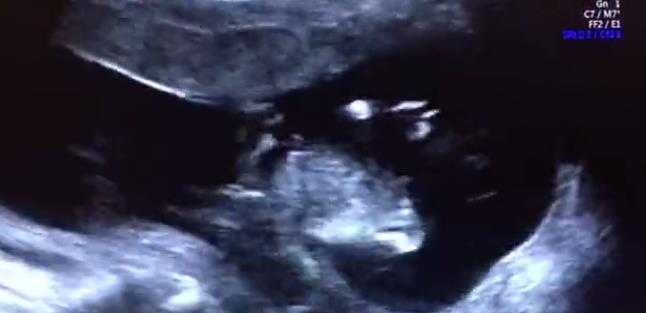

最后,我們再和大家分享兩段

我院四維篩查雙胞胎超聲影像

兩段篩查視頻都是超聲科孫輝醫(yī)生

通過E10四維設(shè)備為雙胎寶媽進(jìn)行的

其中一位是不孕科治療后迎來好孕

而另一位則是產(chǎn)科的產(chǎn)檢分娩客戶